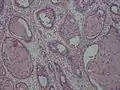

- Adenoid squamous cell carcinoma (also known as pseudoglandular squamous cell carcinoma) is characterized by a tubular microscopic pattern and keratinocyte acantholysis.[18]

Adenoid squamous-cell carcinoma

Adenoid squamous-cell carcinoma Basaloid squamous-cell carcinoma